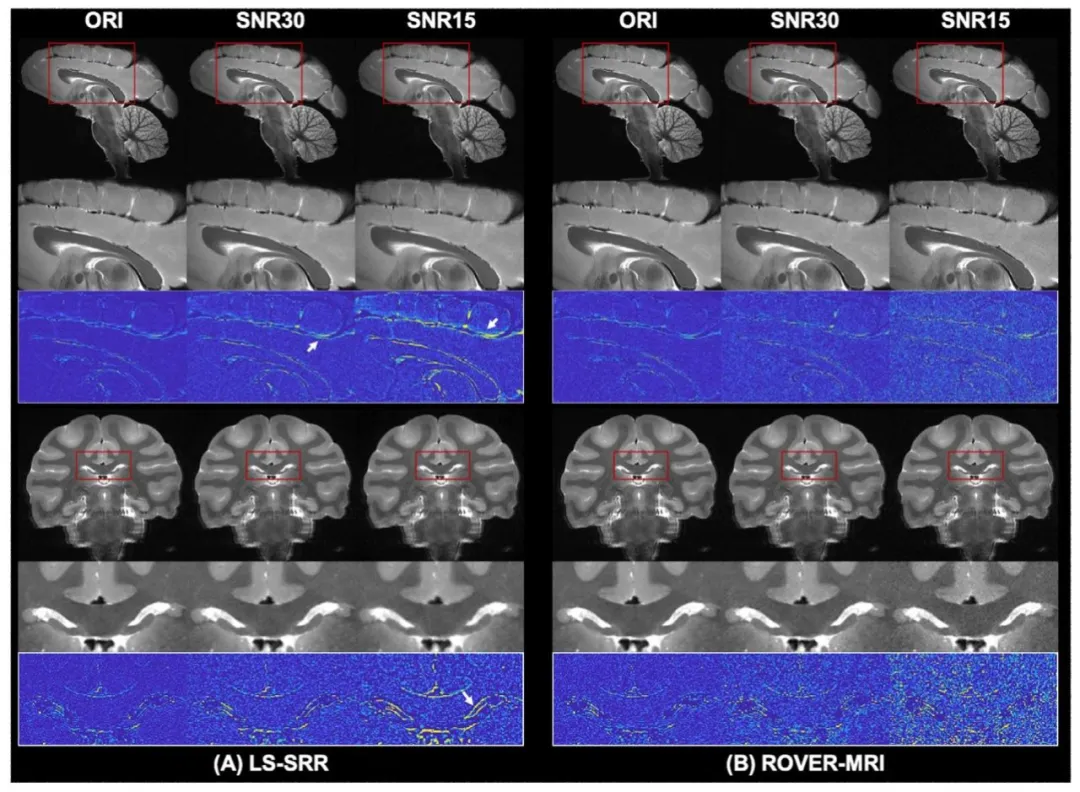

Fig. 4. Reconstruction results of our method and LS-SRR with varying noise levels. (A) LS-SRR results under added noise, where reconstructions at SNR 30 showreduced error compared to SNR 15. (B) ROVER-MRI reconstructs cleaner images with significantly reduced errors compared to LS-SRR at both SNR levels. Rows1 and 4 display typical reconstruction results, while Rows 2 and 5 show enlarged views of the regions within the red boxes. Rows 3 and 6 show the error mapsfor these regions, emphasizing the robustness of ROVER-MRI against noise.

图 4 本方法与最小二乘超分辨率重建(LS-SRR)在不同噪声水平下的重建结果。(A) 添加噪声后的LS-SRR结果,显示信噪比(SNR)为30时的重建误差低于SNR为15时。(B) ROVER-MRI在两种信噪比水平下均能重建出更清晰的图像,且误差较LS-SRR显著降低。第1行和第4行展示典型重建结果,第2行和第5行显示红色方框内区域的放大图,第3行和第6行显示这些区域的误差图,凸显ROVER-MRI的抗噪声鲁棒性。